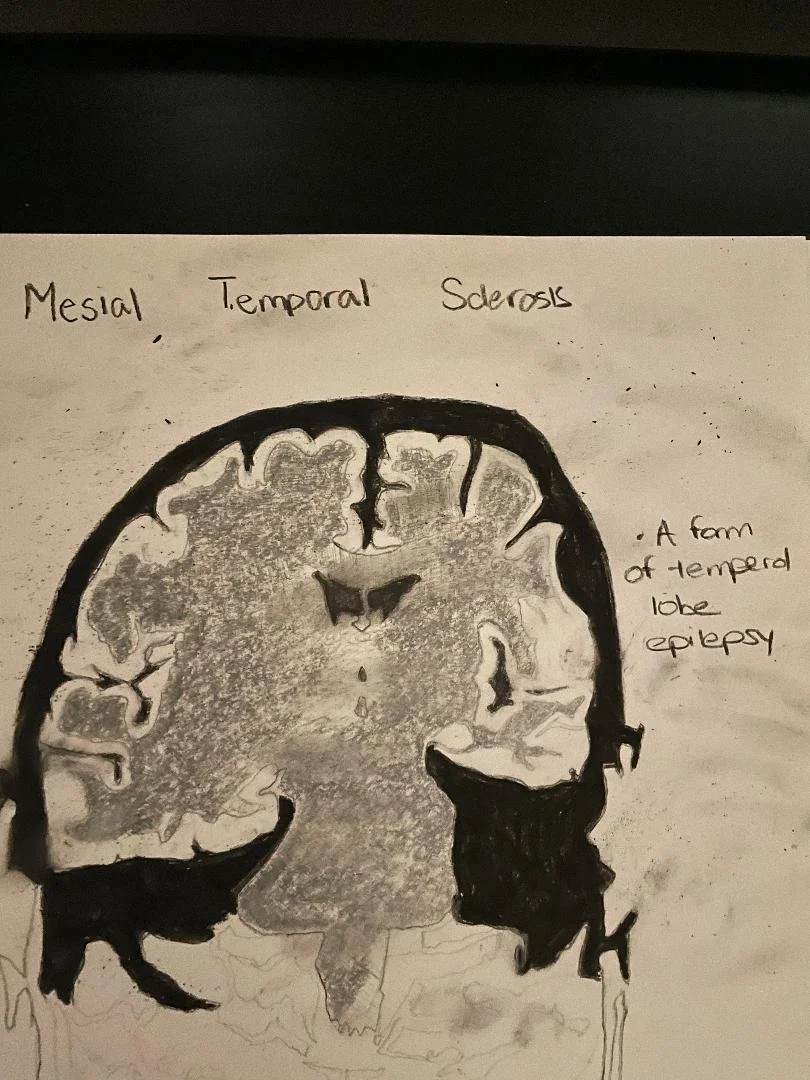

Mesial Temporal Sclerosis